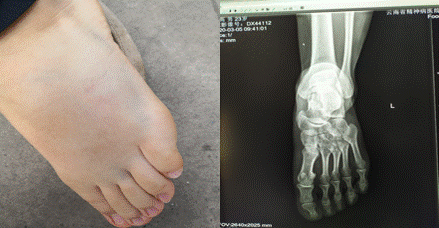

3月3日下午,我院護(hù)士劉高在體溫監(jiān)測點上班過程中遭遇大風(fēng)天氣掀翻了帳篷、桌子造成了足背受傷。

為傳達(dá)院工會對職工的關(guān)懷,我院工會主席柳貴明,護(hù)理部冒才英主任、馬潤娟副主任及譚澍帶上禮品和工會慰問金前去探望職工劉高?,F(xiàn)場了解職工情況,幸在沒有造成骨折,只是肌肉、肌腱受到擠壓引起腫脹,目前平地走路已不成問題,爬樓過程中足背用不上力。柳貴明主席叮囑員工保持良好的心態(tài),多注意休息,減少站立時間,爭取早日恢復(fù)如初。